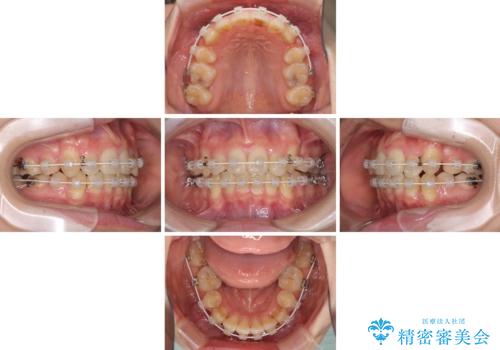

気になる八重歯を治したい ワイヤー装置での抜歯矯正

- 上下の八重歯や乱杭歯を気にして来院され患者様です。

スペースを確保するため、上下左右の第一小臼歯を抜歯し、ワイヤー装置に矯正することとしました。

結婚式の予定があったため、まずは前歯をきれいに整えるようにしました。

結婚式の時には一時的に前歯の装置を外し、口元を気にせず笑える結婚式を迎えることができました。

その後スペースを閉じるために時間を要しましたが、満足のいく仕上がりとなりました。